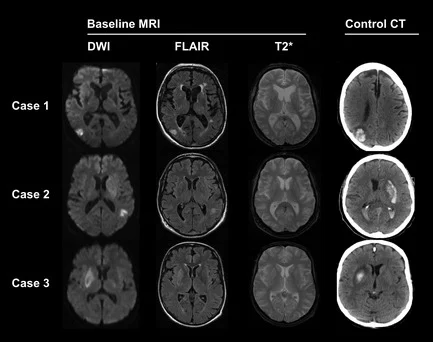

На МРТ гліоз проявляється у вигляді ділянки з підвищеним сигналом на T2/FLAIR, дещо зниженим сигналом на T1 та дещо уповільненою дифузією на ADC. - Мікроінсульти (лакунарні зміни).

Іноді на МРТ можна побачити сліди так званих «тихих» або мікроінсультів — маленьких ділянок пошкодження через порушення кровотоку. Людина могла навіть не відчути симптомів, але такі зміни свідчать про проблеми з судинами та загалом підвищують ризик великого інсульту в майбутньому. У такому випадку лікар зазвичай рекомендує додаткове обстеження та контроль факторів ризику. - Кісти головного мозку.